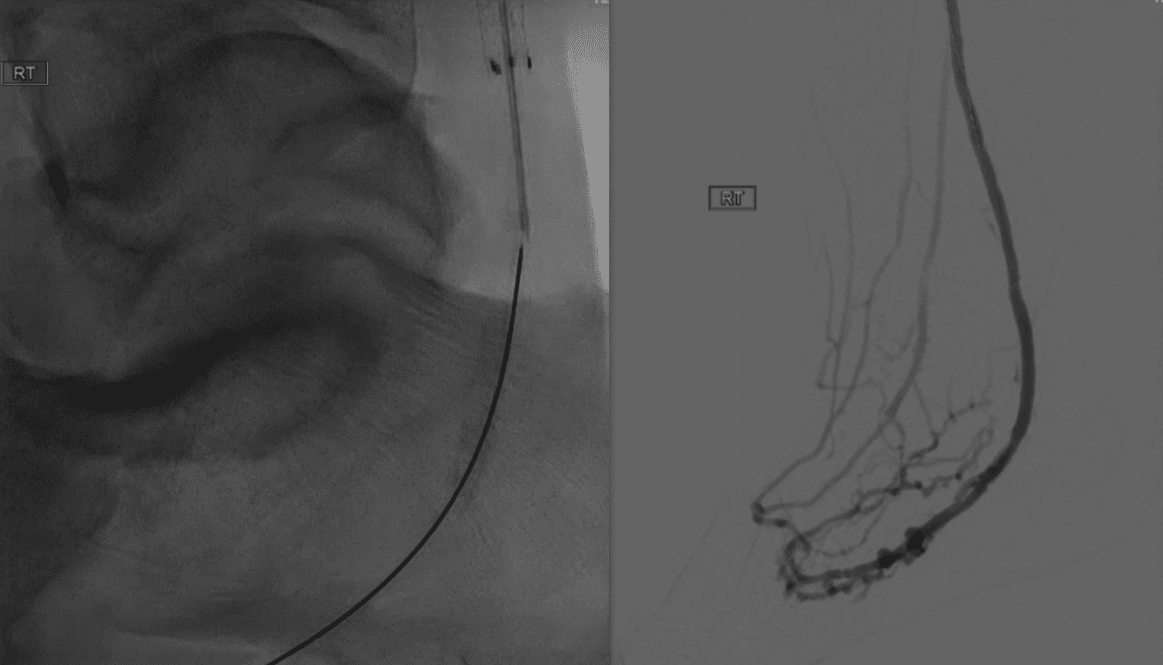

A 74-year-old male with a history of type 2 diabetes, hypertension, morbid obesity, and atherosclerosis of the bilateral extremities presented with an ulcer on the right plantar aspect and a gangrenous third digit on the right foot.